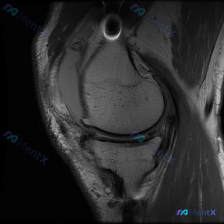

遇到一个挺典型的读片问题,整理出来和大家分享一下思路: 病例背景 临床关注点:怀疑膝关节软骨异常,提供单张膝关节MRI矢状位T1加权像(T1WI)读片 影像基础评估结果 先把影像上能看到的情况理清楚: 1. 骨性结构:股骨远端、胫骨近端皮质连续,没有骨折;骨髓信号是正常脂肪骨髓的灰白色信号,没有局灶...

刚整理了一份很有临床参考意义的病例读片资料,分享一下思路,大家一起讨论。 病例基本信息 临床关注点:患者自述/临床怀疑存在半月板异常,提供单张膝关节MRI T1序列矢状位图像供分析。 影像读片结果 先把读片的核心结果整理出来: 1. 图像与解剖:图像对比度良好,为膝关节矢状位T1序列,可清晰显示股骨...